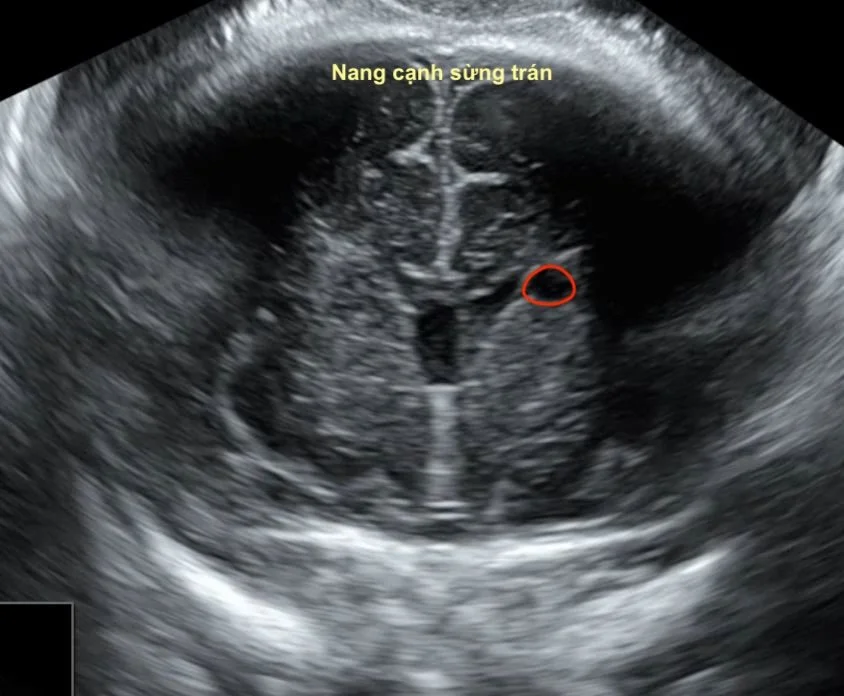

PVPC là cấu trúc dạng nang trống âm, thành mỏng, không có biểu mô lót, nằm sát não thất bên. Thường gặp ở sừng trán não thất hoặc rãnh caudothalamic. Đây là tổn thương có nguồn gốc từ sự thoái triển hoặc vi xuất huyết của vùng germinal matrix trong giai đoạn sinh thần kinh (14–28 tuần).

- Nang tròn/bầu dục, trống âm hoàn toàn, thành mỏng.

- Không thông với não thất, không gây giãn hoặc lệch đường giữa.

- Doppler: không thấy dòng chảy trong nang.

- FHC (Frontal Horn Cyst): ở sừng trán